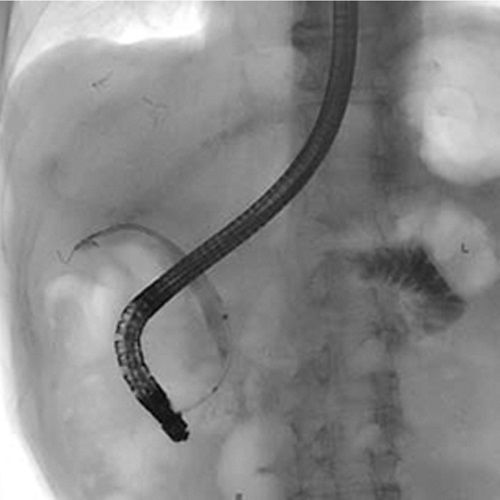

Endoscopic retrograde cholangiopancreatography (ERCP) sagittal view